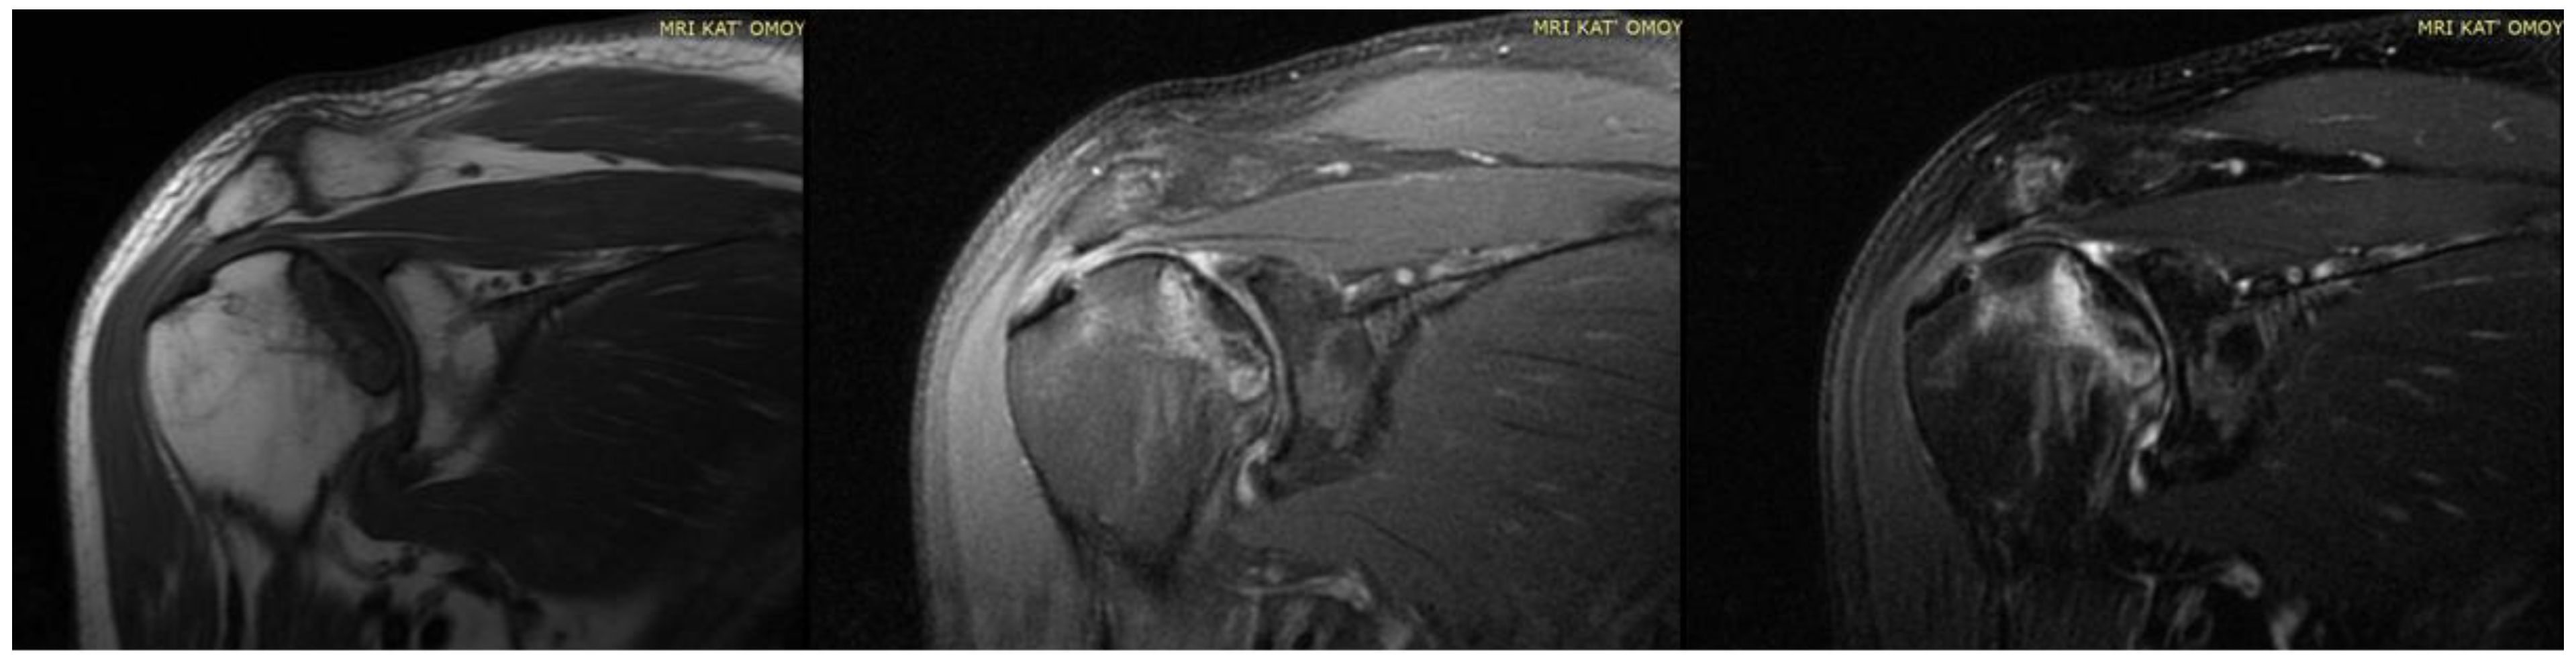

| 14. Kashkosh et al. (2022) [15] | Case report | 1 M | 40 | Second dose of the Pfizer COVID-19 vaccine | AVN of the humeral head | 2 | Analgesics Activity modification IA hydrodilatation inj | Improved ROM Severe shoulder pain Surgical intervention |